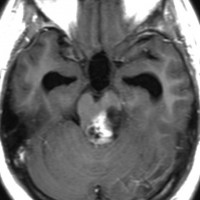

MRIでとても似ている腫瘍

tectal gliomaに間違えそうなPPTID 松果体実質腫瘍

上段のガドリニウム増強MRIでは松果体腫瘍に見えやや境界が不明瞭なので,年齢からはPPTIDが疑われます。しかし,CISSの画像で,中脳上丘との境界がなく中脳腫大があるようにみえ,テクタールグリオーマを疑って経過観察しました。腫瘍がゆっくり増大したので摘出したところPPTIDという診断がつきました。